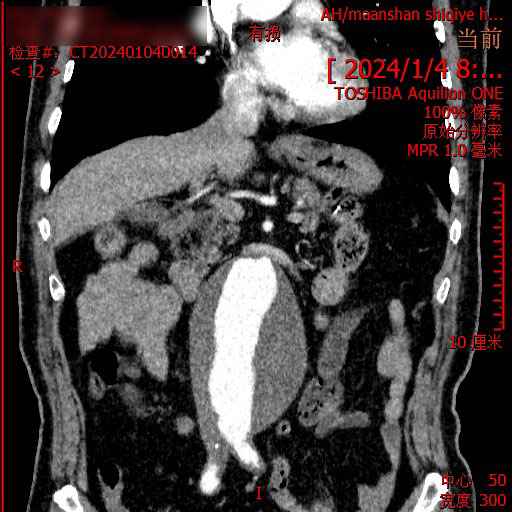

正当一家人走投无路之际,在朋友的介绍下,2024年1月,患者来到了马鞍山十七冶医院肿瘤精准诊疗中心,刘永彪主任携团队亲自为他量身定制了治疗方案,考虑到腹主动脉夹层,同时召集医院感染科、老年病科、心血管内科、肿瘤科等专家进行会诊。经过一系列的检查,明确病情,直肠中分化腺癌,虽然有手术指征,但伴有腹主动脉巨大瘤,手术风险极高,综合考虑建议先进行放射治疗,患者家属听到可以治疗如释重负,喜极而泣。

2024年1月,患者开始精准定位,进入肿瘤内科进行放射治疗,过程中,主任和他的团队每日至少查房两次,以便观察患者的病情变化,及时调整放疗计量,减少并发症给患者带来的痛苦。因为腹主动脉瘤的高危性,整个治疗过程中,医护人员操作轻柔,治疗仔细,减少副反应给患者腹部带来的刺激。没想到经过第一阶段的放射治疗后,患者的病情便得到有效缓解,便秘、腹泻等症状逐渐减轻。“简直就是奇迹!真没想到放射治疗效果就那么好,这让压在我们心口的石头终于落了地,十七冶医院肿瘤精准诊疗中心的专家医术高明,医德高尚,是咱马鞍山老百姓的福气。”患者家属夸赞道。